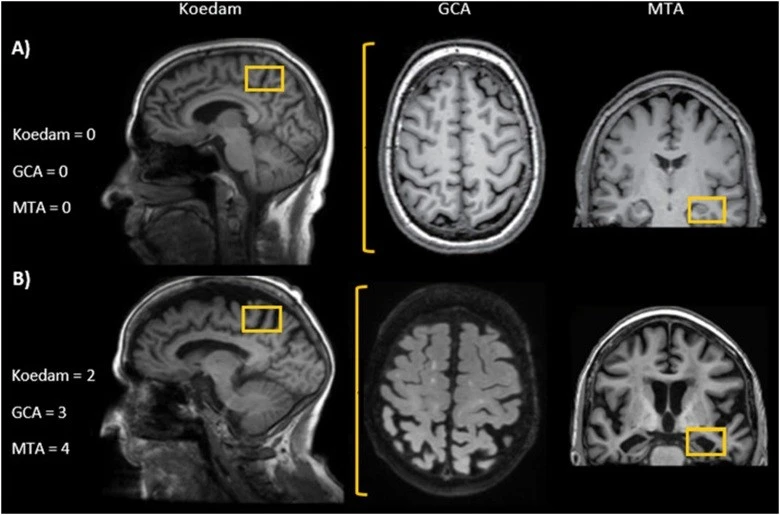

An analysis of over 12,000 MRI scans from nearly 5,000 healthy people aged 17 to 95 showed that brain volume declines faster in men than in women. Specifically, men exhibit greater loss of gray and white matter in more regions, including the cerebral cortex and subcortical structures.